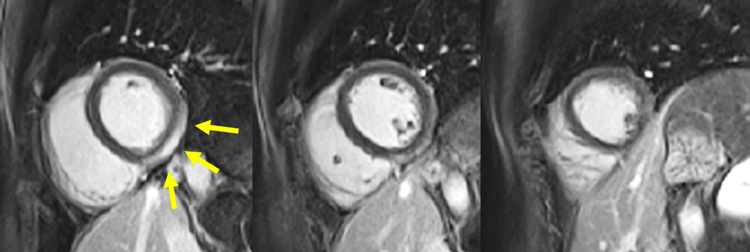

Figure 1A : Séquence Ciné-IRM - Coupes petit-axe basal

Figure 1B : Séquence Ciné-IRM - Coupes petit-axe médian

Figure 1C : Séquence Ciné-IRM - Coupes petit-axe apical

Figure 1D : Séquence Ciné-IRM - Coupes 2-cavités

Figure 1E : Séquence Ciné-IRM - Coupes 3-cavités

Figure 1F : Séquence Ciné-IRM - Coupes 4-cavités